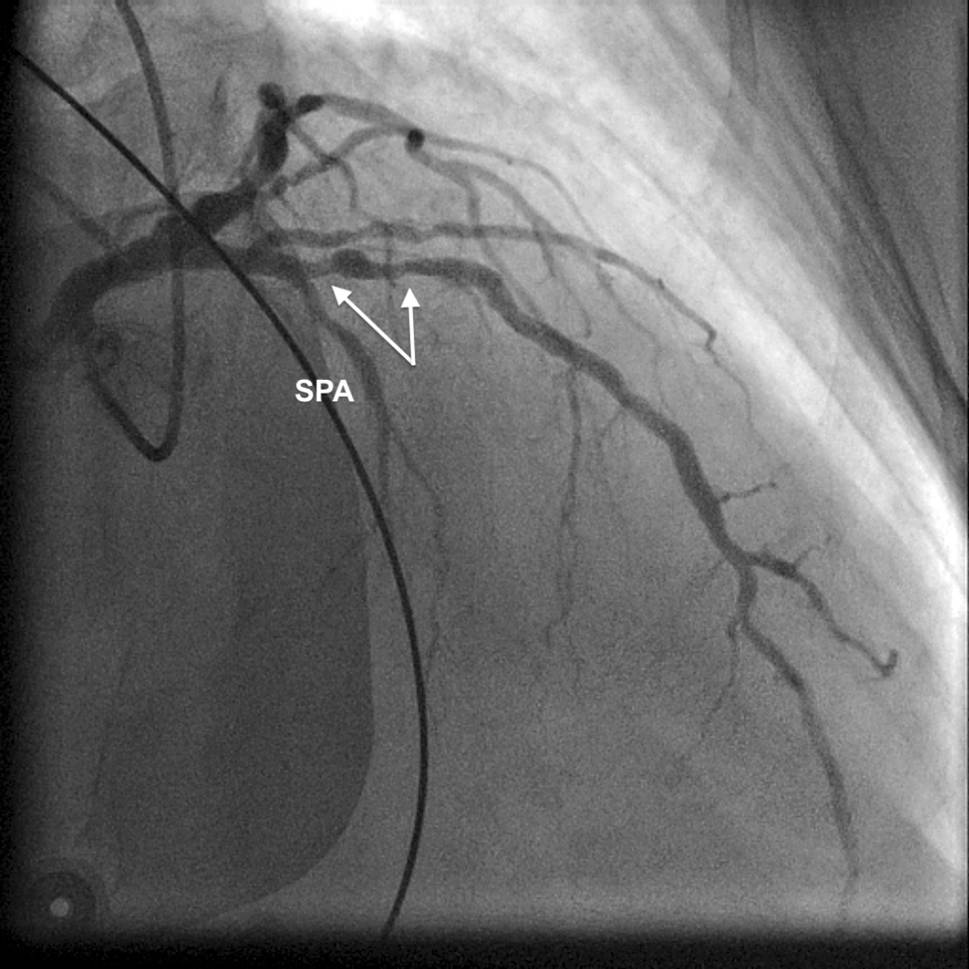

Electrocardiography (ECG) during angina showed an ST-segment elevation resembling the Greek letter λ (lambda) and a striking increase in R wave amplitude (> 15 mm) in leads V2–V5 (prominent anterior QRS forces), loss of septal Q waves in V5–V6 and ST-segment elevation in II, aVF and III (Fig. 1). Emergency angiography revealed an obstructive stenosis in the proximal left anterior descending (LAD) coronary artery (Fig. 2), which was successfully treated with stenting.

Fig. 2

Conventional coronary angiography image depicting obstructive stenosis (arrows) in proximal left anterior descending coronary artery. First septal perforator artery (SPA), which arises immediately proximal to the stenosis, is also shown

ECG showed intermittent changes compatible with a conduction disturbance or block in the left septal fascicle (LSF), which is a third distinct division of the left bundle branch proceeding to the middle third of the left septal surface towards the apex [1]. Indeed, of all causes of prominent anterior QRS forces, only left septal fascicular block (LSFB) can manifest as intermittent ECG changes [1]. Durrer et al. demonstrated breakthrough activation through the LSF by using isolated, perfused human hearts, thereby for the first time proving its existence [2]. Ischaemia-induced LSFB has been associated with lesions in the proximal LAD coronary artery, the septal branches of which provide the entire blood supply of the LSF [1]. In our patient, ischaemic ST-segment elevation and LSFB were probably due to vasospasm at the site of the LAD artery lesion compromising blood flow in the first septal branch found in the immediate vicinity.